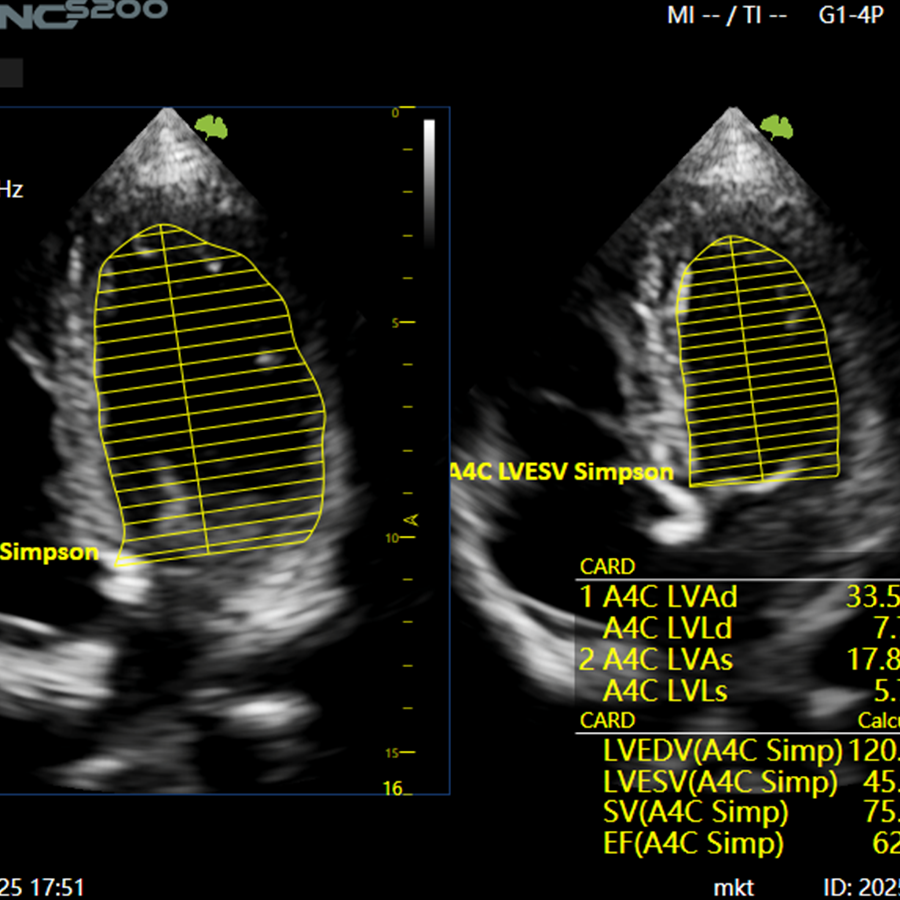

Cardiología

- EF Automática

- Auto EF